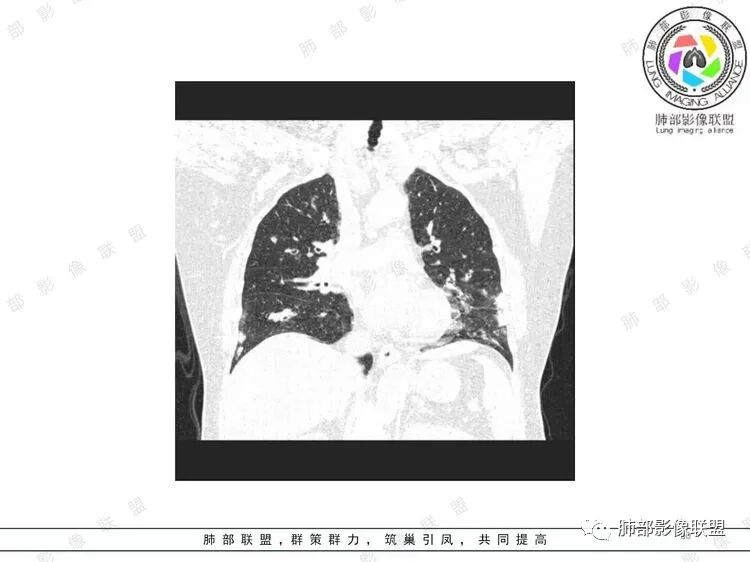

胸CT:双中下肺支气管壁明显增厚,双下肺胸膜下可见实变区。部分病变呈楔形影。

双肺支气管管壁弥漫性增厚,管腔狭窄,下叶为主,伴多发高密度结节影,边缘模糊,双肺支气管血管束明显增粗,临床症状咳嗽低热,有血尿,首先考虑血管炎

支气管壁增厚,两下肺为主,沿支气管血管束分布斑片状、结节状病变,中轴间质增厚。疾病谱可能有:1.气道来源疾病:结核、曲霉、支原体等;2.间质来源疾病:血管、淋巴系统。结合有血尿,使用激素后尿色变淡、抗生素治疗效果差等病史,考虑血管炎可能性大。

影像上:多发结节沿血管分布;双下叶支气管血管束简直增厚,偏血管,支气管通畅

膀胱炎症

肠系膜血管周围有渗出

左上颌窦粘膜下囊肿,鼻甲肥厚

右肾结石

首先肺部气道来源的病变不符合

因为支气管壁增厚,远端应该小气道病变,这个不是,反而是血管增粗明显

加上结节的分布,支持血管相关病变

累及范围广泛:肠系膜血管?膀胱